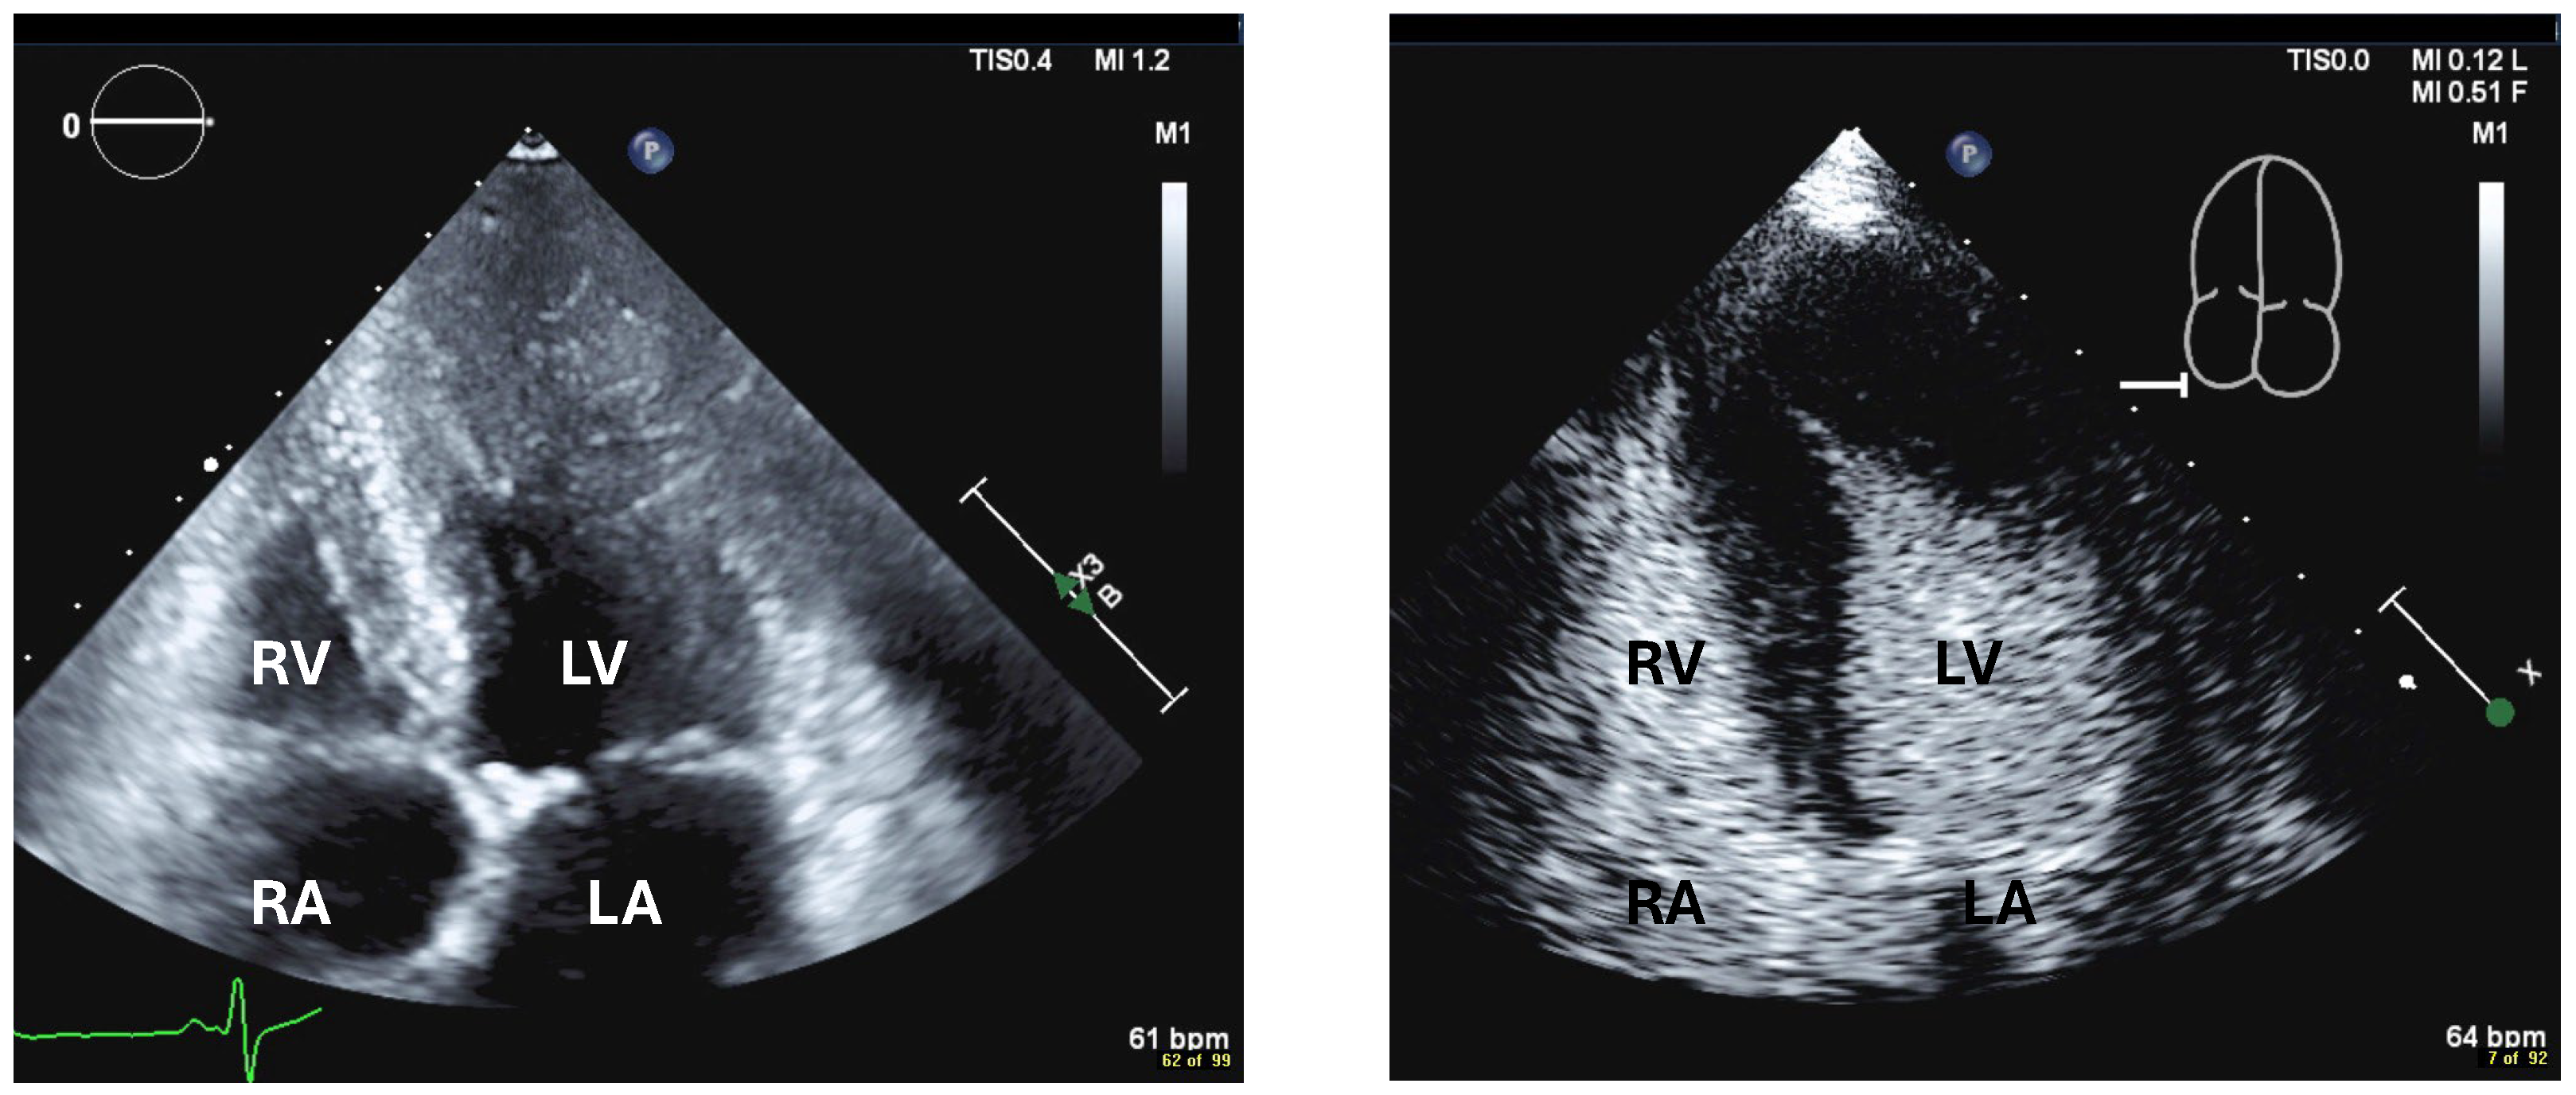

| Imaging method | start with low-MI-contrast-specific imaging for assessment of global and regional LV function then use intermediate-MI-contrast-specific imaging which provides better display of LV trabeculations |

| Imaging planes | standard apical views parasternal and apical short-axis view |

| Contrast application | bolus injection |

| Typical findings | trabeculated layer apical, lateral, and inferior: more than 3 trabeculations, ratio of trabeculated/compact myocardium >2 The number of trabeculations and the ratio of trabeculated/compact myocardium does not seem to impact clinical management |

| Alternative imaging | MRI for tissue characterization in dilated cardiomyopathy and risk assessment in hypertrophic cardiomyopathy, assessment of LV thrombi when CEUS recordings are non-diagnostic |